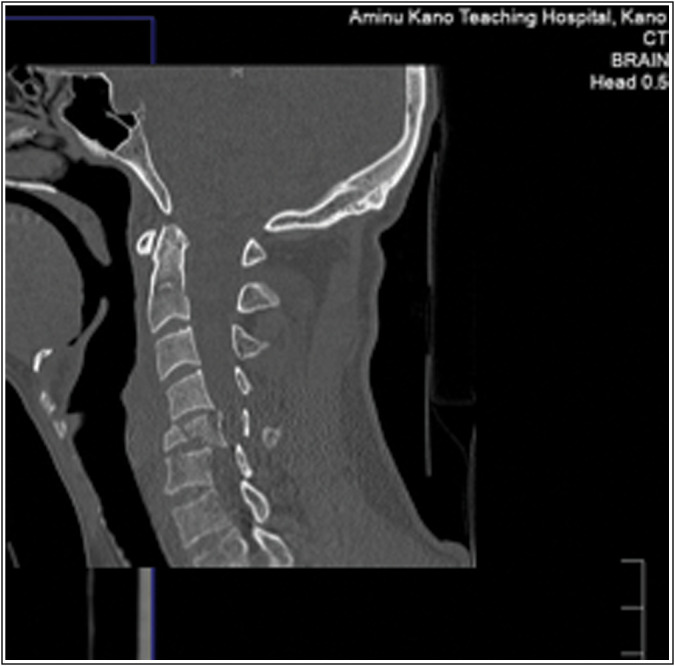

Results: There were 143 patients with head injuries studied; 90.2% of them were males. The mean age of the patients was 28.87 ± 15.93 years. The most common cause of injury was road traffic accidents in 110 (76.90%). The prevalence of CSI was 11.2%. Majority of the patients with CSI in this study (56.25%) had a mild head injury, 25% had a moderate head injury, and 18.75% had a severe head injury. The lower cervical spine was the most frequently injured segment in this study, involving 10 patients. Multi-level cervical vertebral body fractures of C3 to C6 were the most common form of CSI in this segment.

Abstract Image